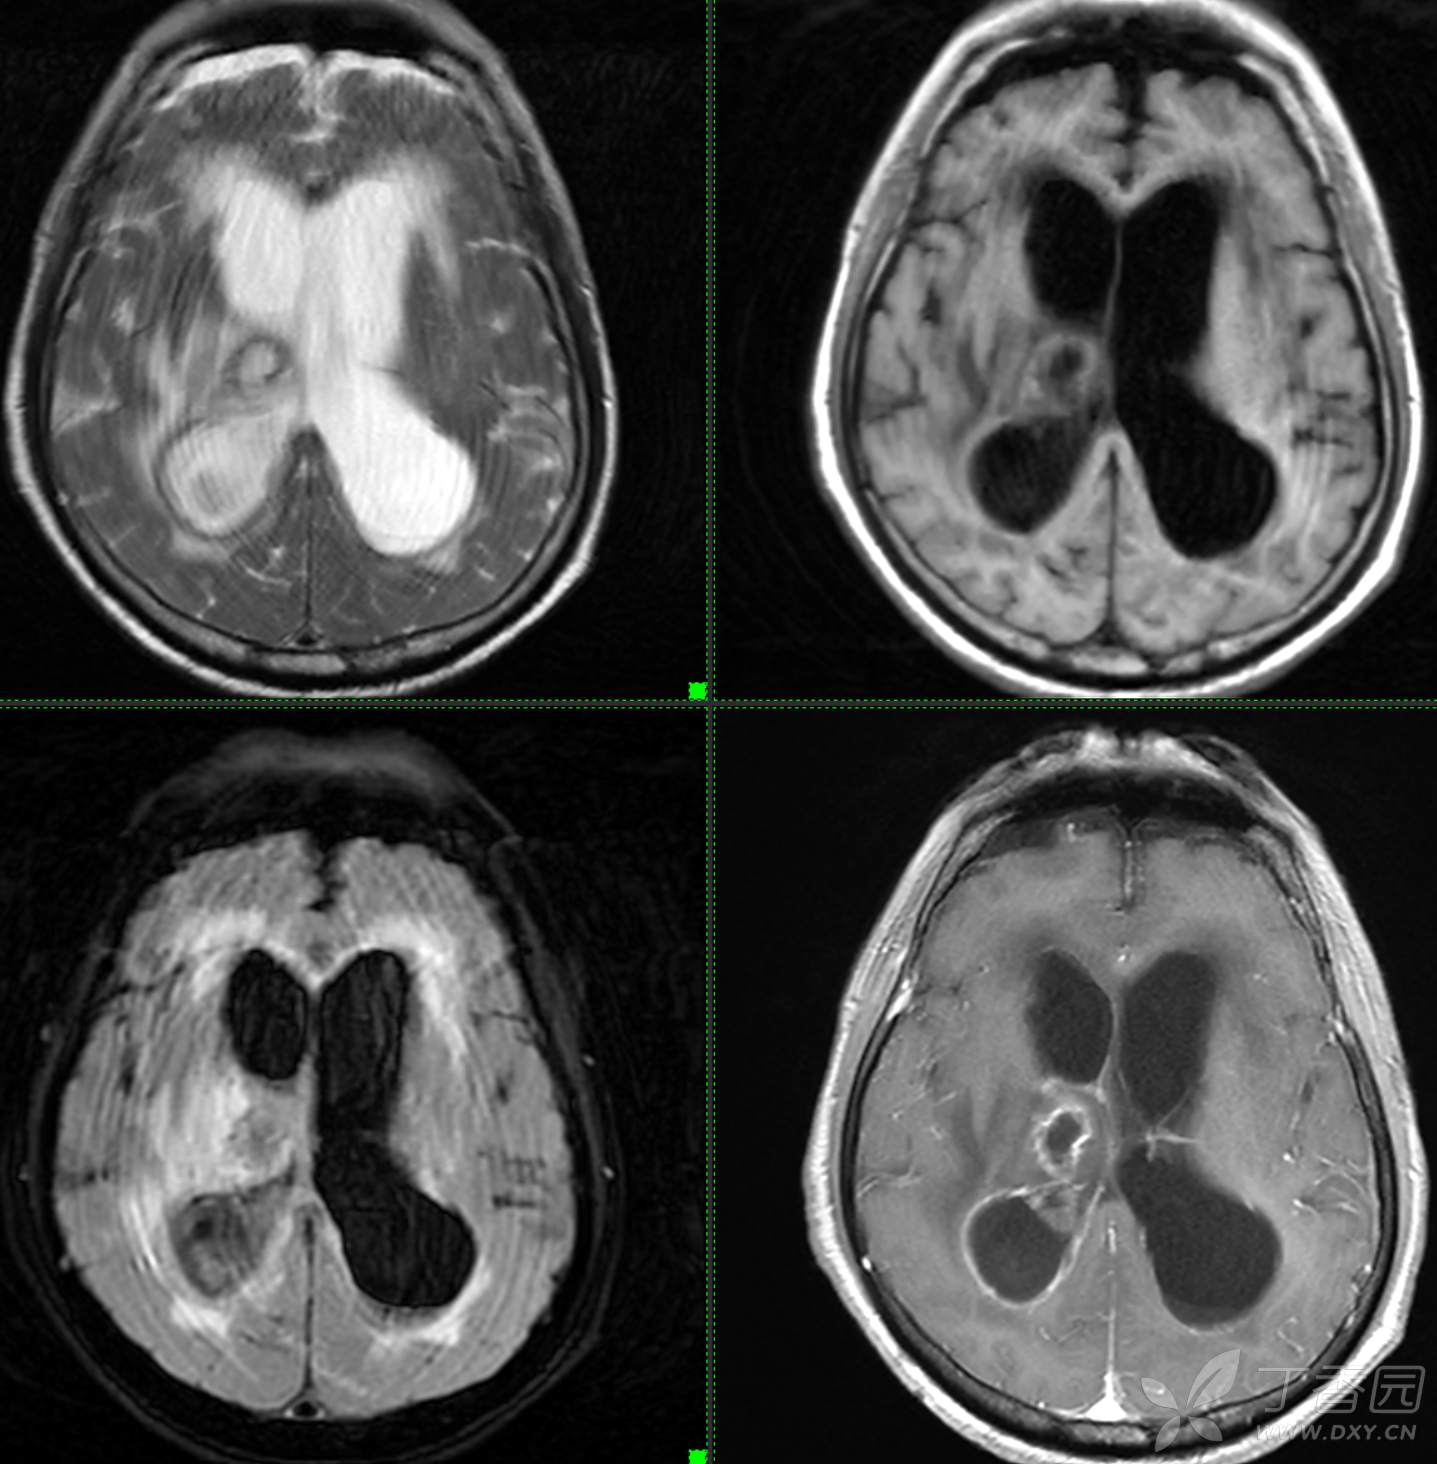

头颈组9:简单分析,诊断不难。

主诉: 【头晕乏力数周,发热1周】

现病史: 患者3周前无明显诱因下出现头晕,无头痛,伴视物模糊,肢体乏力,走路步态不 稳,无意识不清,对答切题,当地医院查血常规示:中性粒细胞分类:77.7%.淋巴细胞分类:15.6%,中性性粒细胞分类:7.1*10^9/L.葡萄糖:22.35mmol/,头颅平扫示:右侧丘脑饱满,密度减低伴低密度灶,占位不排除,两侧半卵圆区、额叶低密度灶,以“1.糖尿病酮症酸中毒,2.颅内占位性病变”收入住院治疗,1周前住院期间出现发热,先后予抗感染,控制血糖等对症支持治疗,2天前无明显诱因下再次出现发热,伴血糖升高,自测体温40℃,血糖20mmol儿,伴气促无胸闷,袖志模糊,反应迟钝,无畏寒寒战,无腹痛腹泻等不适,昨日送至我院就诊